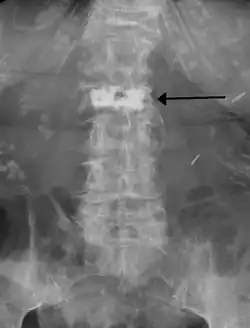

Sam zabieg nie trwa długo. Przeprowadzany jest w znieczuleniu ogólnym, podpajeczynówkowym lub miejscowym. Przeprowadzający zabieg wbija igłę w staw międzykręgowy, wprowadza ją do trzonu i po wykonaniu szeregu czynności kontrolnych podaje przez igłę cement kostny wzmacniający dany krąg. Następnie igła jest wycofywana, a miejsce wkłucia zabezpieczane opatrunkiem. Cała operacja śledzona jest w czasie rzeczywistym na podglądzie RTG. Pacjent zwykle wypisywany jest ze szpitala po 12-24 godzinach.